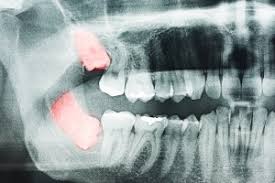

완전히 나오지 않은 사랑니를 빼는 건 복잡한 수술 중 하나라고 한다.

하악골(아래턱뼈) 속에는 입술과 잇몸의 감각을 느끼게 하는 신경이 지난다고 한다.

상악골(위턱뼈) 속에는 축농증이 일어날 수 있는 부분인 상악동이 있다고 한다.

이들이 사랑니 뿌리와 근접하거나 겹쳐 있는 경우가 종종 있다고 한다.

이때는 콘빔형전산화단층촬영(CBCT)을 포함한 사전 검사와 평가 후 수술을 받는 것이 좋다고 한다.